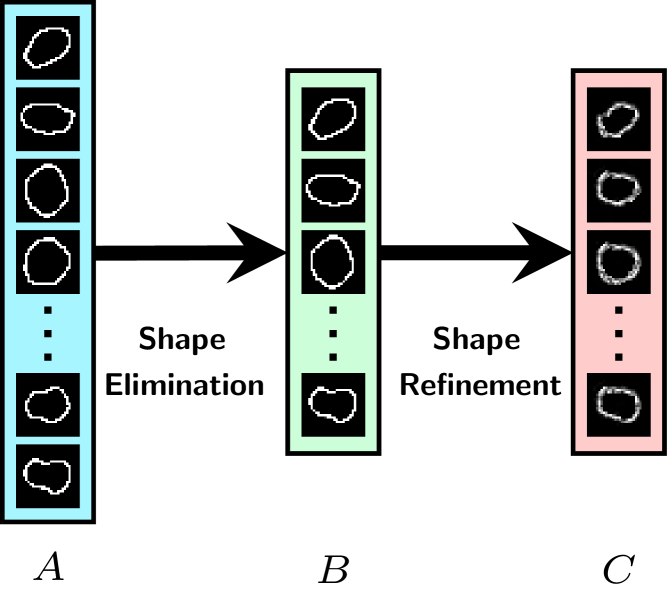

We observe that the domain expert provided shape set in practice is quite redundant, i.e. it may contain pairs of hand-crafted shapes that are quite close to each other and do not add value to nucleus detection. We therefore propose a two stage process to arrive at a compact Basis Shape Set which is adapted based on training imagery: 1.) shape elimination stage to obtain a reduced/smaller reference shape set, and 2.) shape refinement or learning via TSP-CNN. This two stage process is illustrated in Fig. 5. For both stages, meaningful shape similarity measures are needed; the exact shape elimination and refinement procedure is detailed next. We next introduce shape elimination and refinement procedures, and then describe the training procedure to learn shapes that are adapted to the underlying dataset.

Starting with the domain expert provided shape set , we eliminate redundancy by using the aforementioned CW-SSIM measure to compute pairwise comparisons of shapes. Near identical (redundant) shapes are grouped together and one representative is extracted from the group. The complete procedure is detailed in Algorithm 1.

The output of Algorithm 1 is what we address as the Reference Shape Set – which is essentially a cardinality (size) reduced version of the domain expert provided shape set , i.e. . Our approach to learn or refine shapes is then to optimize a Learnable Shape Set under the important physical constraint that the shapes in bear similarity to those in .